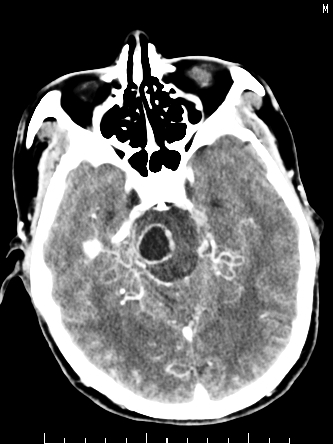

m/50,头昏头痛1月,近3天感觉左半肢体活动不利,自述半年前呈患肺tb,腰穿脑脊液未见特殊改变。现做头颅ct请大家会诊。

考虑:1.结核脓肿,2.星形胶质瘤,但脑积液正常,这考虑肿瘤的可能性大些.期待结果

首先考虑肿瘤性病变,星形细胞瘤可能性大,不排外转移瘤。建议mri。

结核性脑膜炎,结核瘤,梗塞灶三症并存,提示颅内结核感染可能性大。

脑干占位,考虑转移瘤可能性大,不除外胶质瘤.

考虑为:脑干脓肿;不排除胶质瘤或转移瘤。

可考虑结核,患者水肿范围大,囊性病灶边缘密度较高,不考虑胶质母细胞瘤